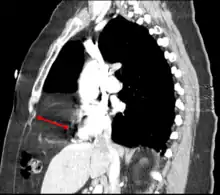

The Bochdalek hernia, also known as a postero-lateral diaphragmatic hernia, is the most common manifestation of CDH, accounting for more than 95% of cases. In this instance the diaphragm abnormality is characterized by a hole in the postero-lateral corner of the diaphragm which allows passage of the abdominal viscera into the chest cavity. The majority of Bochdalek hernias (80–85%) occur on the left side of the diaphragm, a large proportion of the remaining cases occur on the right side. To date, it carries a high mortality[3] and is an active area of clinical research.